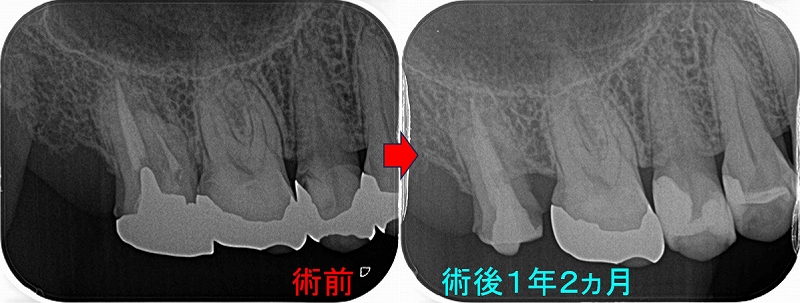

分割確認のレントゲン

ヘミセクション後 フルジルコニアクラウンを入れさせてもらったのですが・・・

クラウンを入れて2年半後にコアごとクラウン脱離

骨の所見を見ると、咬む力による問題+クラウンに強すぎる材料を使ってしまったここと推測

患者さんに謝り、もう一度根管治療からやり直させてもらいました。

ヘミセクションの際に自分がレジンコア作るべきだったと反省。。。

仮歯を入れて経過を見て行き

ようやく1年、骨もしっかり戻ってきてくれています。

この後、クラウンは弱目の材料で作っていこうと計画しています。